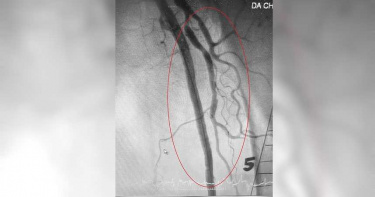

隨著冷氣團不停報到,民眾經常出現四肢「凍未條」的狀況。一名七旬婦人日前發生下肢冰冷、疼痛、蒼白及麻木等症狀,因此轉院到高雄醫學大學附設中和紀念醫院,經過醫院血管攝影檢查,發現婦人是「腳中風」的急性下肢動脈栓塞,醫師團隊立即藉由機械性血栓抽吸設備及溶栓術,將婦人慘變「烏骨雞」的下肢搶救回來。一名七旬婦人因下肢冰冷、疼痛、蒼白及麻木等症狀到他院就醫,經過外院醫院血管攝影檢查,發現婦人有下肢動脈栓塞情況,因此轉院到高醫進行處置,高醫團隊經確認婦人狀況後,藉由機械性血栓抽吸設備及溶栓術將婦人栓塞的腳部搶救回來。「腳是人的第二心臟」高醫緊急周邊血管團隊主要召集人許栢超強調,周邊血管疾病不是只靠心臟科打通血管就好 它是需要跨領域團隊來共同照護的疾病,心臟血管內科這些年在周邊導管治療的進步,幫助民眾保肢且救命,就是希望能讓民眾的2個心臟都一樣強大。許栢超教授進一步表示,一般通稱的心血管疾病,包含了心臟血管、腦血管,以及周邊血管疾病等,只是民眾常把周邊血管疾病給忽略了,過往因為民眾對於周邊血管疾病的認知有限,再加上早期導管的治療效果不佳,且設備不夠精良,因此最後患者常面臨截肢的悲慘命運,甚至可能因此失去生命。高雄醫學大學附設中和紀念醫院副院長戴嘉言表示,過往大家對於心血管疾病的認知,主要在冠狀動脈疾病和腦血管疾病,往往忽略周邊血管疾病也是重要的環節,以嚴重肢體缺血病人為例,如果肢體傷口不易癒合,據文獻資料,3年後的死亡率可高達5成。但常見下肢深層靜脈栓塞也可能致命,下肢深層靜脈栓塞的主要症狀是單側患肢腫脹,嚴重者會因血栓跑到肺部造成可能致命的肺栓塞,若無好好治療,長期下來也可能造成栓塞後症候群,如靜脈潰瘍、肺高壓等問題,緊急的導管搶救就成了拯救肢體和生命的關鍵。